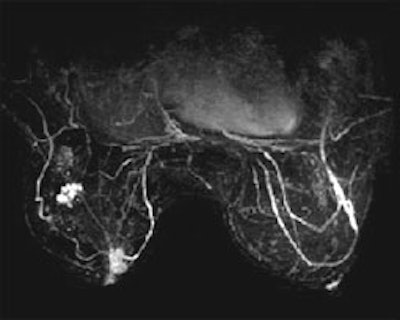

Past breast MRI protocols have encountered a trade-off -- better resolution has required a sacrifice in temporal resolution. Now, because of SpiralRODEO's improved acquisition efficiency (3 times greater than traditional 3DFT reconstruction), resolution is dramatically increased along with a significant decrease in scan time for better dynamics.

The result of this new breakthrough is image quality far superior in clarity and contrast than ever before possible -- actually offering signal improvement comparable with that of 4.5 Tesla -- at a significantly less cost!

See the difference in these SpiralRODEO™ 3D images: